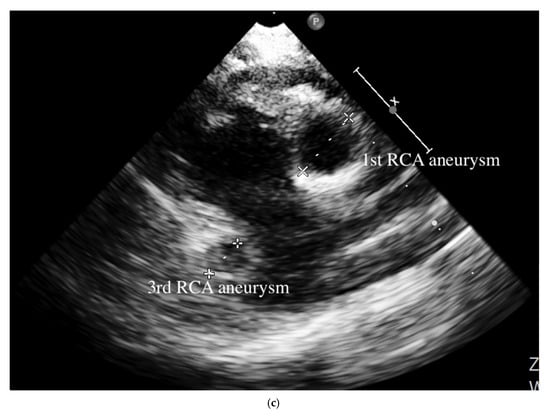

A 4-month-old infant girlwho presented with intermittent fever without explanation for 14 days was admitted.Laboratorydata revealed leukocytosis (19.5 × 109/L), high sensitivityC-reactive protein (CRP, 1139.04 nmol/L), and thrombocytosis (590 × 109/L). Negative culture reports were found in blood and urine. The empirical antibiotics administration did not achieve clinical improvement. The subcostal view of echocardiography andtransthoracic echocardiography (TTE) revealed three giant fusiform aneurysms of the proximal right coronary artery, along with other smaller aneurysms in the left coronary system. (Figure 1) Acute mitral insufficiency with moderate pericardial effusion was also present. The three beaded aneurysms were subsequently confirmed on a selective right coronary angiogram. (Figure 2) The fever resolved after receivinga high-dose intravenous immunoglobulin (IVIG) infusion. Aspirin with anticoagulant drugs (subcutaneous injection of low molecular weight heparin) administration was initiated and serial echocardiography as well as invasive coronary angiography follow-up were regularly performed sincethe giant aneurysm’s detection. (Figure 3) This report revealeda “beaded aneurysm” as a special medical image for KD.Itsfundamental nature of non-contiguous aneurysms could be a key to identifying antecedent KD vasculopathy compared toother coronary artery aneurysms. Written informed consent was obtained from the participant for the publication of this case report.

A pediatrician must check the echocardiography imaging of coronary arteries in infants with prolonged fever and evidence of elevated inflammation markers whenever the reasonable cause is absent because positive echocardiography findings were regarded as a set standard for acute KD accordingly. Coronary aneurysms can occur in up to 25% of KD children without a timely infusion of high-dose IVIG such as in this index case.As coronary aneurysms have become rare due to the widespread use of IVIG therapy for KD, beaded aneurysm is considered to be even rarer. There are no reports on the frequency of beaded aneurysms in KD, but it is presumed to be relatively rare.The final size of coronary aneurysms defines the future risk stratification generally speaking. In small or medium-sized aneurysms (<8mm or Z score <10), spontaneous regression of the aneurysms without significant cardiovascular sequela such as long-term luminal myofibroblastic proliferation is possible. In this case, the subcostal view of echocardiography and TTE revealed three giant fusiform aneurysms of the proximal right coronary artery, along with other smaller aneurysms in the left coronary system (Figure 1a–c). The three beaded aneurysms were confirmed by coronary angiogram is showed in Figure 2. In contrast with smaller aneurysms, giant aneurysms (>8 mm or Z score >10) seldom or never regress over time, which could be observed from the timeline of the index case(Figure 3).

Figure 2. Selective right coronary aneurysm was showed in this figure. Right coronary angiogram showed a beaded pattern of a saccular/fusiform aneurysm.